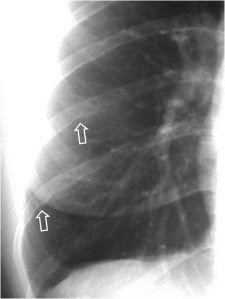

SIGNO DE LA CISURA INCOMPLETA, DE LA PSEUDOCAVIDAD O SIGNO DE LA ESPINA DE ROSA

Es un signo de derrame pleural en la cisura mayor visible en la radiografía de tórax, en un paciente con cisura mayor incompleta. Es más frecuente verlo en el lado derecho ya que en el izquierdo la silueta cardiaca puede ocultarlo.

La presencia de una zona radiotransparente perihiliar, circunscrita lateralmente por una línea curva bien marcada (flecha blanca), en cuya periferia se observan varios grados de opacidad, corresponde a la presencia de líquido en la cisura mayor incompleta. La línea curva termina en un extremo en punta (flecha roja), que estará más cercana al hilio cuanto más completa sea la cisura.

El nombre de pseudocavidad hace referencia a la radiolucencia perihiliar, mientras que el de espina de la rosa se refiere a la morfología de la opacidad, con el extremo en punta.